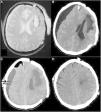

Hinged craniotomy (HC) is an alternative surgical technique that can be used in place of decompressive craniectomy (DC) to treat refractory intracranial hypertension. This procedure has the advantage of avoiding the need for a second surgery to replace the bone, while giving a good control of intracranial pressure. However, there is no consistent literature about complications of HC. In particular, there are no reported cases of contralateral subdural effusion (CSE) after HC. In this article we present a case of a 55-years-old man who developed CSE after a hinged craniotomy (HC) for intracranial hypertension, and how we handled it. Therefore, we explored literature to better understand the pathogenesis of CSE, treatments and possible prevention strategies.